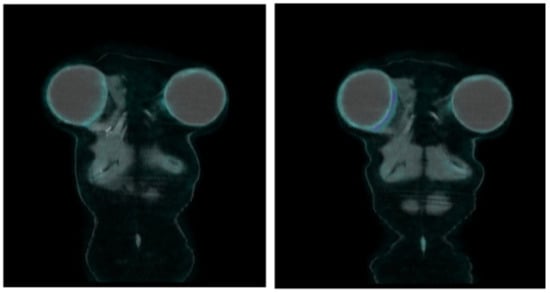

| [18F]FDG PET/CT | -No uptake or only faint uptake around the breast implant. -No axillary lymph node uptake, or just faint uptake in normally-sized nodes, vascular hilum well-visible. | -Focal uptake around the implant and in axillary, mediastinal (usually internal mammary), and supraclavicular enlarged lymph nodes; -Pericapsular fluid collection may be present, with detectable faint activity; -Fluid effusion between the breast implant and the host fibrous capsule causing asymmetry and swelling of the breast can be a sign of breast implant-associated anaplastic large-cell lymphoma. | Even bearing in mind the clinical history of each patient, both visual and semiquantitative analysis (SUVmax) do not discriminate among inflammation, infection, and neoplastic foci, because they take up glucose similarly. The clinical setting of each focal uptake (implantation for oncological versus aesthetic reasons) and any morphological findings (see above) may lead the clinician to follow-up or to collect a biopsy specimen, and eventually fluid culturing, to rule out granuloma/infection versus node metastases or lymphoma or SCC associated with breast implants. |